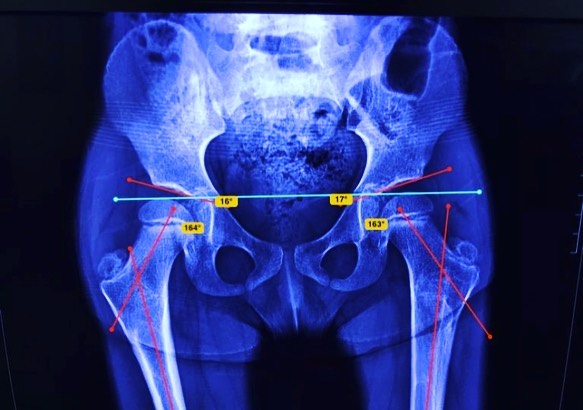

Quiero compartirles que doy de alta a mi pacientita Leilany, de 5 años. La operé por displasia de cadera causada por coxas valgas (región proximal del fémur muy vertical), que alteraba la morfología de su cadera y provocaba disfunción a largo plazo. Le realicé un tratamiento quirúrgico para corregir la deformidad y ahora está al 💯, lista para jugar y hacer travesuras. 🎉